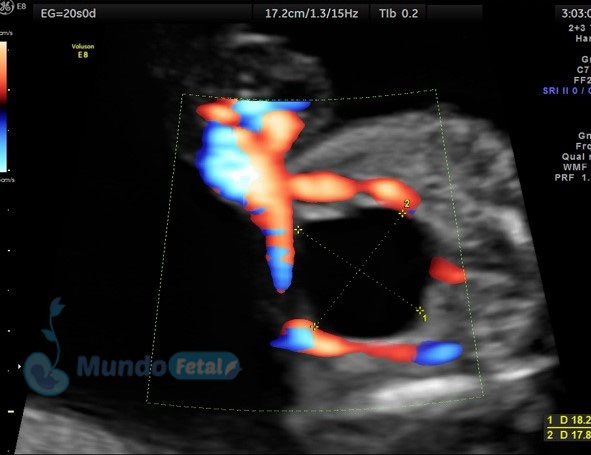

Ultrasonido 2do Trimestre 18-23 Semanas (Estructural o Anatómico)

Entre las 18 y 22 semanas, el feto ha desarrollado la mayoría de sus estructuras anatómicas, permitiéndonos valorar de manera detallada todos los órganos del bebe, descartando anomalías anatómicas fetales y datos de cromosomopatías. Prediciendo además preeclampsia (Doppler de arterias uterinas) y parto prematuro (por medio de la medición de la longitud del cérvix). En manos expertas, la detección de anomalías anatómicas supera el 80%.

ANATOMICO-VEJIGA